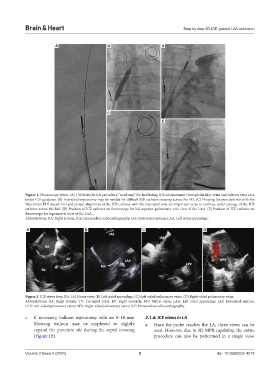

Figure 1. Fluoroscopy views. (A) J Wire in the RA provides a “road map” for facilitating ICE advancement through the iliac veins and inferior vena cava

under ICE guidance. (B) Interatrial septostomy may be needed for difficult ICE catheter crossing across the IAS. (C) Flossing the puncture site with the

Watchman FLX sheath first and proper alignment of the ICE catheter with the transeptal wire are important steps to facilitate easier passage of the ICE

catheter across the IAS. (D) Position of ICE catheter on fluoroscopy for left superior pulmonary vein view of the LAA. (E) Position of ICE catheter on

fluoroscopy for supramitral view of the LAA.

Abbreviations: RA: Right atrium; ICE: Intracardiac echocardiography; IAS: Interatrial septum; LAA: Left atrial appendage.